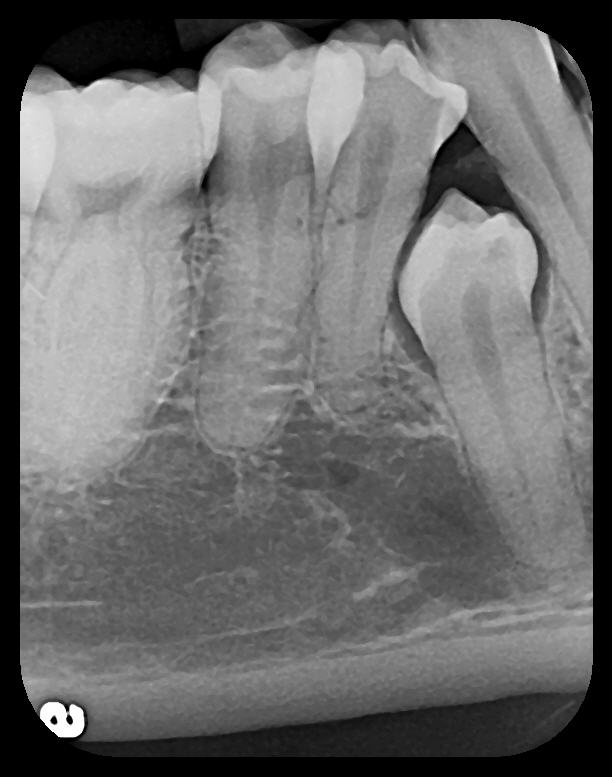

Fig 4. Severe dilaceration of root of tooth No. 17 and

curvature of roots of No. 18. Mandibular canal and inferior border of mandible are

easily visualized. If extraction of No. 17 is planned, a 3D CBCT study is required

due to proximity of tooth root to vascular and inferior alveolar nerve contents of

mandibular canal and possibility of surgical complications.

Figure 4